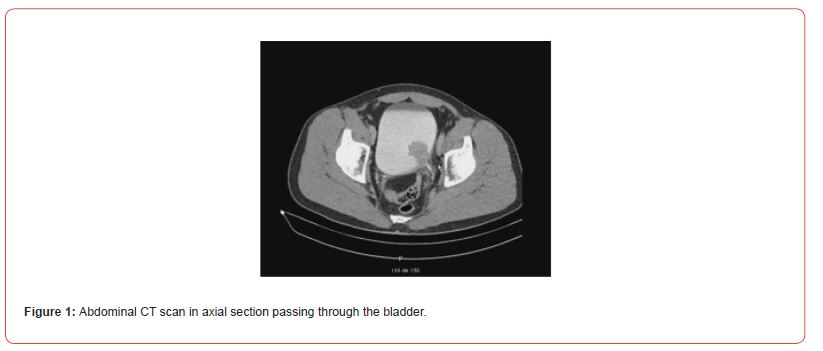

A 49-year-old patient presented with macroscopic hematuria. The CT scan revealed a protruding mass measuring 4 cm on the left postero-lateral wall of the bladder (Figures 1&2). Cystoscopy showed a fleshy polypoid mass near the left ureteral meatus. Bladder cancer was suspected, and an endoscopic resection was performed. Microscopic examination showed that the different samples involved the bladder wall, with a predominantly fusiform myofibroblastic cell proliferation arranged in a fascicular pattern and associated with inflammatory cells. At other locations, there were more star-shaped cells arranged in a myxoid stroma associated with inflammatory cells (mixed infiltrate characterized by neutrophils, eosinophils, plasma cells, lymphocytes). The myofibroblastic cells infiltrated the bladder wall diffusely. There was extensive invasion of the submucosa and invasion of the muscular layers. Some areas of tumor necrosis were present. The mitotic index ranged from 4 to 6 mitoses per 10 high-power fields. Many hemorrhagic changes were associated with this tumor proliferation. The tumor was invasive and poorly defined. Surface ulceration occurred.